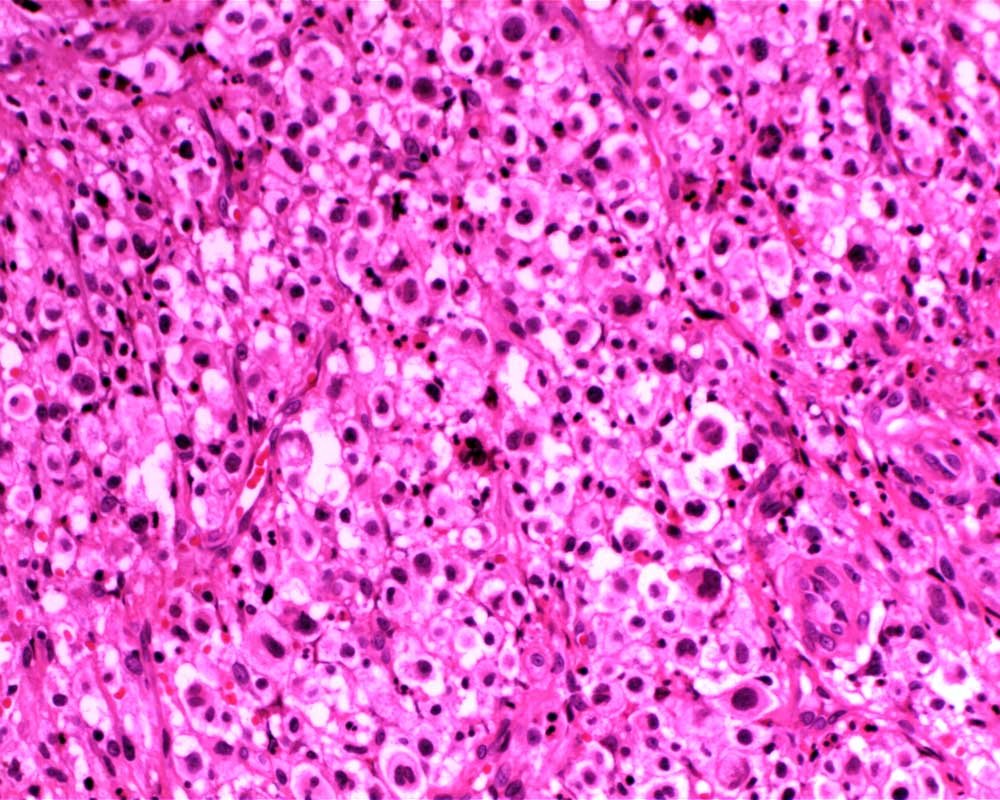

Case: FemurLesion

Final Diagnosis: